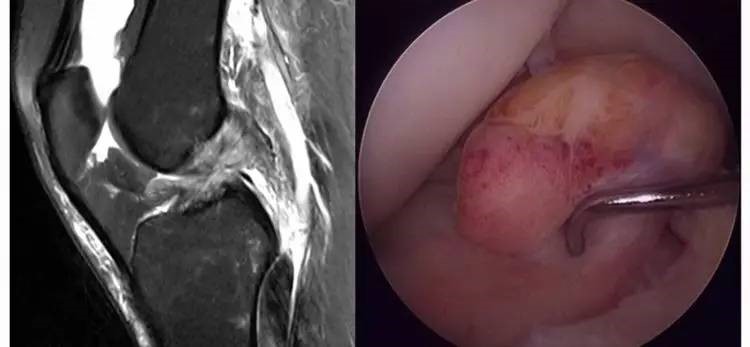

5.假瘤:韧带损伤后断端较整齐,残端组织增生并被滑膜包裹呈'瘤状',如果突出于前方为'独眼征',多见于韧带股骨附着部撕裂及部分撕裂。